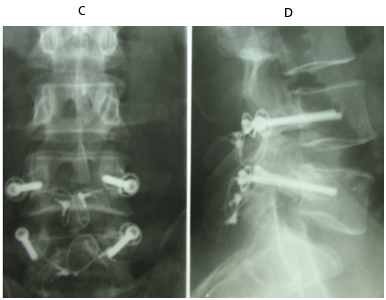

No implant failure was detected in the follow up radiographs. At the final follow up, radiological healing could be achieved bilaterally in all patients (86.6%) but four. Three of them had initial defects >3mm and one from 2-3mm, all at L5. For the healed cases, the mean time to union was 4.7 months. In the cases which did not heal, only 1 complained of significant back pain at final follow up. The other 3 did not complain of pain at final follow up (Figures 3 & 4).

Figure 4 A 23 years old female with double level spodylolyis at L4 and L5. (A, B) Preoperative plain radiographs. (C,D) 3 months after direct pars repair with cable screw construct at both levels.